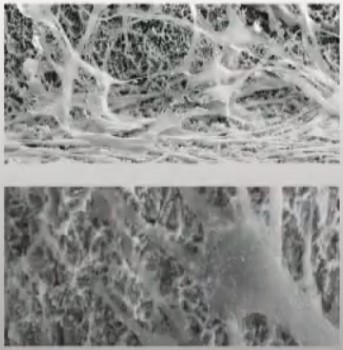

A dental Implant is a titanium “root” that integrates directly with the surrounding bone and replaces the function of the natural tooth. Neoss Implants are made using the best quality medical grade titanium, which is well known for its proven biocompatibility, and have a treated surface to facilitate bone integration.